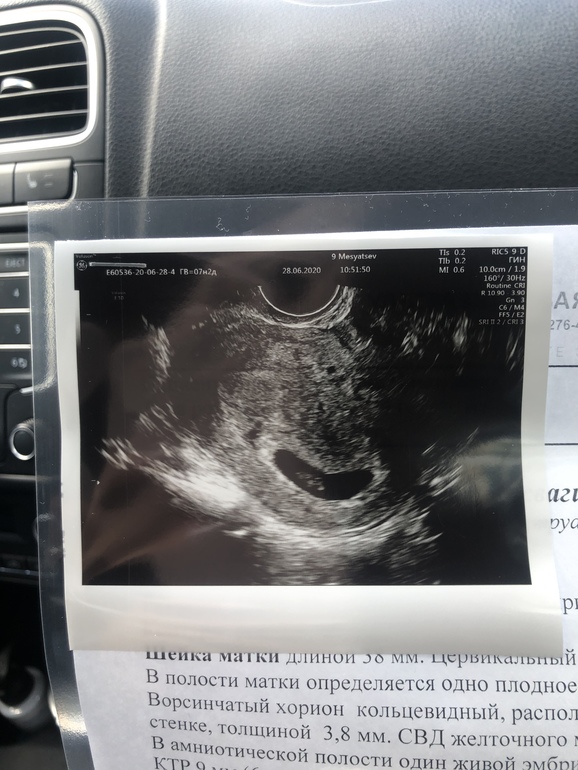

По М. срок 7 недель 2 дня.

СВДПЯ - 19 мм

КТР - 9 мм

СБ + 130 ударов 🤗

ЖМ - 3,6 мм

Хорион по передней стенке - 3,8 мм.

По УЗИ поставили 6 недель 6 дней.